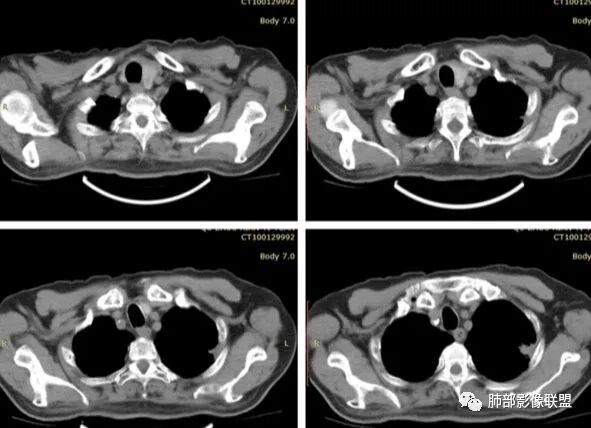

有栽赃吗?

这种属于宽基底与胸膜相连,附近胸膜增厚

栽赃是局部外侵犯

这里没有栽赃

如下图病例红色箭头的是典型栽赃:

南边 :

而该病例栽赃不明显,与增厚的胸膜分界比较清晰

下面这个病例这也是栽赃